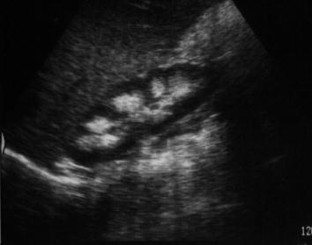

Fig. 1